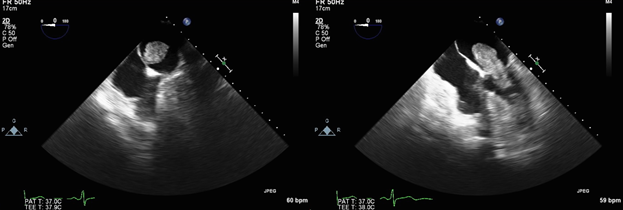

During her hospital stay, a brain magnetic resonance imaging (MRI) was obtained which revealed multiple punctate acute infarcts in bilateral frontal lobes, parieto-occipital lobes, and left cerebellar hemisphere (Figure 1). As the MRI findings were highly suggestive of cardioembolic stroke, a transthoracic echocardiogram was then performed which revealed a large, highly mobile mass attached to the interatrial septum that prolapsed into left ventricle during diastole. A transesophageal echocardiogram confirmed the left atrial mass (Figure 2). The patient underwent a successful surgical resection of the left atrial mass on hospital day 4, which was pathologically confirmed as a 4.0x2.5x1.9 cm cardiac myxoma. She was discharged on postoperative day 6 to home with asprin and atorvastatin for secondary stroke prevention. She has followed up in clinic for two years without recurrence of stroke.

Figure 2 Transesophageal echocardiogram revealing a large, highly mobile mass attached to the interatrial septum that prolapses into the left ventricle during diastole.